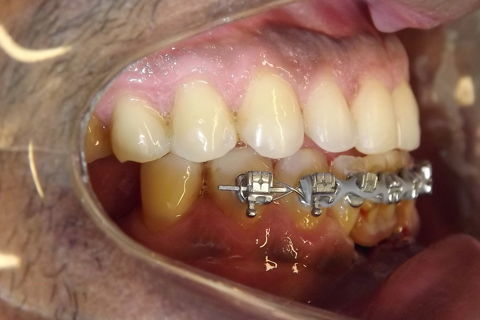

fotos finais, paciente encaminhado para implantes.

Paciente do sexo masculino, 36 anos, brauifacial. Relatava que os Diastemas lhe incomodavam muito, e em tratamento anterior o profissional fez exo de 2 incisivos centrais inferiores e instalou Prótese movel com 4 incisivos, após um tempo de uso a prótese começou a incomodar. em planejamento com o implantodontista ficou definido o fechamento dos diastemas e reabilitação dos elementos 41 e 31 com implantes.